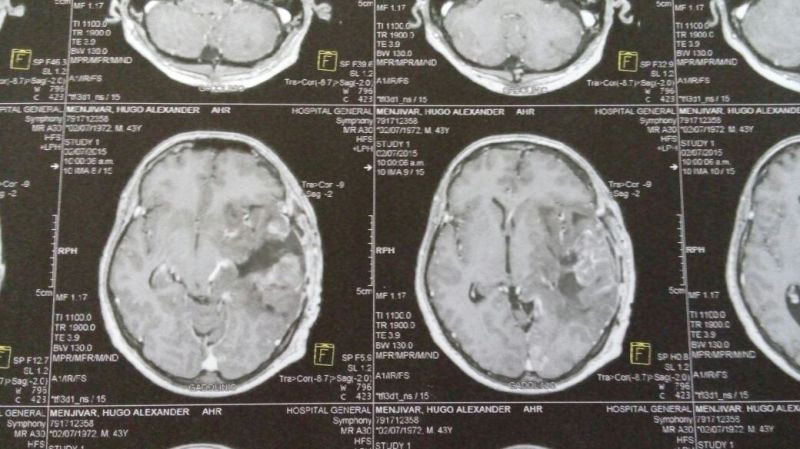

Oligodendroglioma temporal izquierdo Imagenes MRI Preoperatorio

Oligodendroglioma temporal Imagenes MRI Preoperatorio